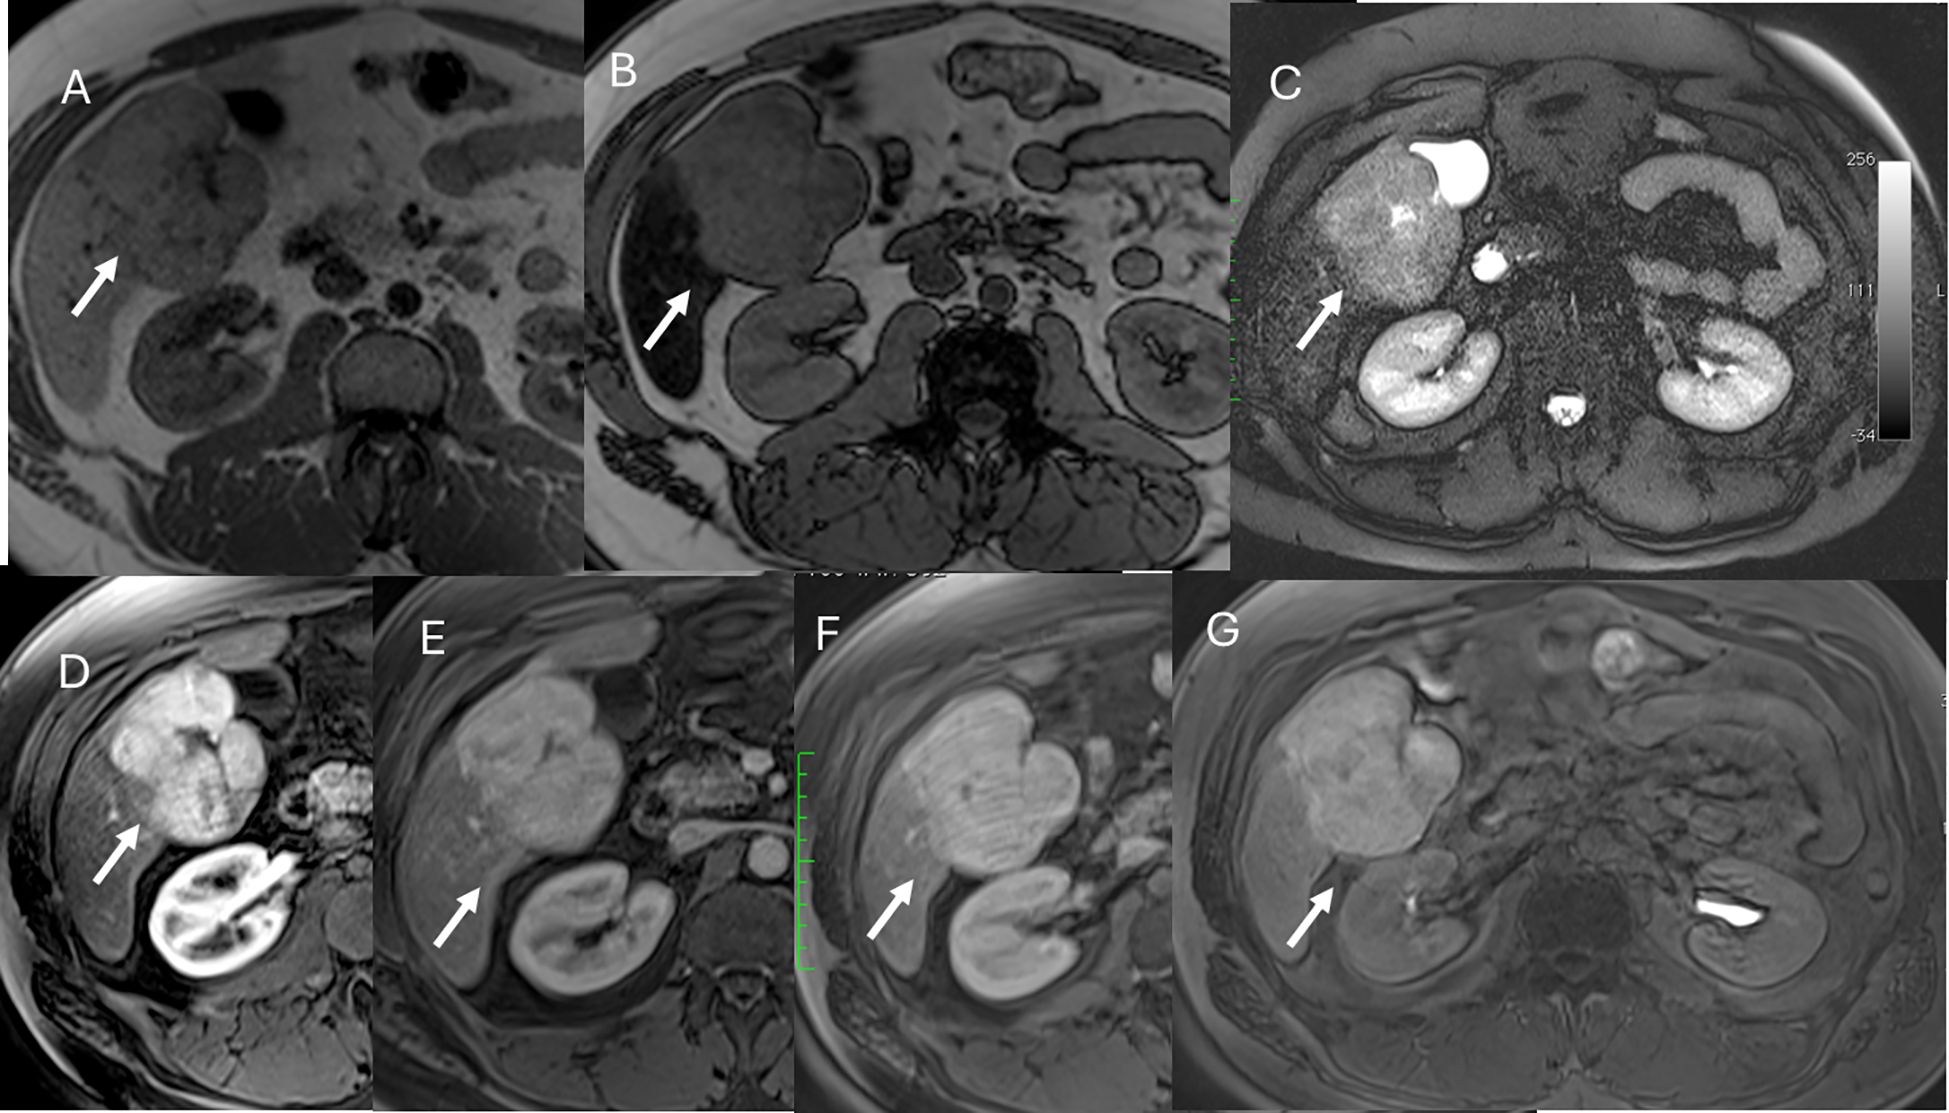

Currently, the most widely used specific agents are those taken up by hepatocytes. These include two types: gadolinium ethoxybenzyl dimeglumine, also known as gadoxetate dimeglumine (Gd-EOB-DTPA; marketed as Primovist in Europe and Eovist in the US, Bayer HealthCare), and gadobenate dimeglumine (Gd-BOPTA; MultiHance, Bracco, Milan, Italy). Although both can be injected as intravenous boluses, they show different contrast kinetics. Gd-BOPTA behaves similarly to non-specific contrast media and allows better vascular assessment. By contrast, studies with Gd-EOB-DTPA are characterized by early uptake by hepatocytes, beginning at about 5 min. Consequently, there is no true late phase; instead, a transition phase is observed (90). In addition, the quality of the arterial phase can be compromised by motion artifacts (Figure 6)—an important factor to keep in mind when selecting contrast for studies requiring high-quality arterial imaging. However, the introduction of artificial intelligence algorithms appears to improve arterial phase quality in Gd-EOB-DTPA studies (91–94).

Figure 6. MRI assessment of colorectal liver metastases with Gd-EOB-DTPA contrast during multi-arterial phase: motion artifacts on all phases with low image quality. (A–C) Sequence acquired on 3T VIDA System (Siemens, Germany) with deep learning AI technology.